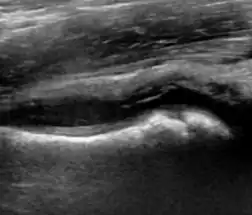

During childhood, ultrasound is a quick method to assess hip pain and quite often may be used to avoid use of irradiating techniques, such as radiography or CT. Ultrasound allows evaluation of joint effusion, synovial thickening and neovascularity, the bone/cartilage contour, and the femoral head-neck alignment. Although sonography is extremely sensitive in detecting increased synovial fluid, it is nonspecific and cannot be used with accuracy to determine the type of fluid. Transient synovitis of the hip, despite being the most frequent cause of pain in children between 3 and 10 years, remains a diagnosis of exclusion. It usually shows anechoic fluid, but echogenic fluid can also be found. The effusion is considered pathologic when it is measured at >2 mm in thickness. The differential diagnosis is wide, including osteomyelitis, septic arthritis, primary or metastatic lesions, LCPD, and SCFE. Discrimination from septic arthritis is challenging, often requiring joint aspiration. In septic arthritis, US is able to demonstrate a hip joint effusion, synovial thickening, and cartilage damage, although the appearances are nonspecific.[1]

A step between the head and the physis can be detected in children with SCFE, while abnormalities in the femoral head contour may suggest the presence of LCPD. In both cases, radiographs are mandatory to confirm diagnosis and severity (Figure 12).[1]

Figure 12:

-

Normal ultrasound appearance of the femoral head-neck junction. -

Joint effusion in transient synovitis of the hip. -

Flattening of the femoral head in a patient with Perthes disease. -

Step in the femoral head-neck junction in a patient with SCFE.